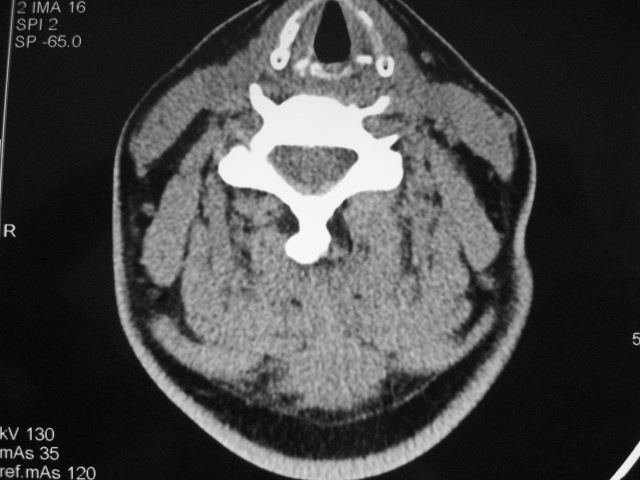

女,46岁,发现颈后区肿块3月余.

颈后软组织肿块,内可见坏死区及点状钙化,邻近颈椎棘突可见破坏,邻近肌间隙模糊,肿块周围脂肪间隙可见索条状影。

考虑:1)感染,结核可能;

2)肿瘤不能排除。

考虑:起源于项韧带的硬纤维瘤可能性大,建议活检进一步检查。

颈后部结核性脓肿可能性大,侵犯临近颈椎棘突,建议进一步检查并照胸片。